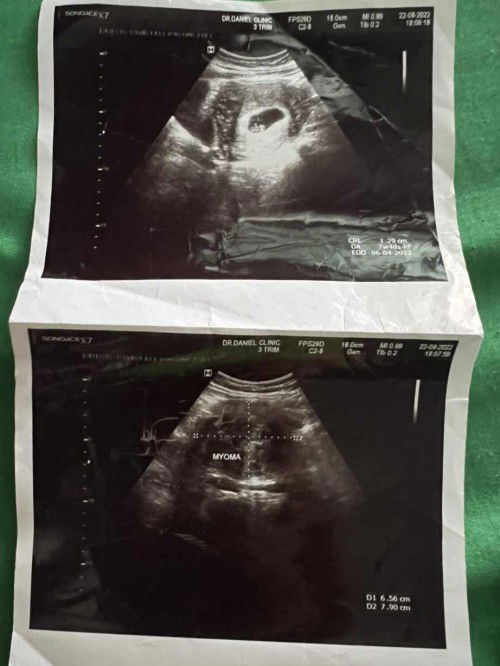

ตรวจพบเนื้องอกขณะตั้งครรภ์เครียดมากท้องแรกด้วยค่ะ อายุ38ค่ะ ใครเจอเหตุการณ์แบบนี้บางค่ะ รูปบนคือน้องค่ะรูปล่างคือก้อนเนื้องอก

ตอนนี้เครียดมากๆๆๆค่ะกลัวไปทุกอย่าง